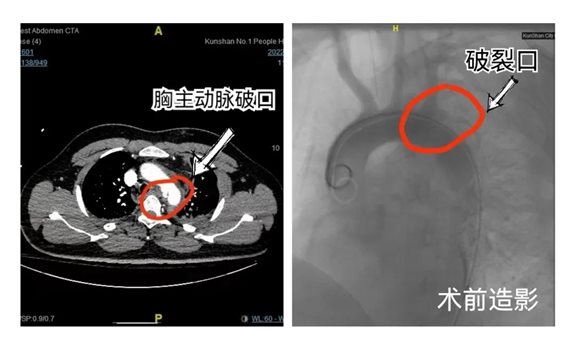

年轻的李先生很不幸发生了车祸因遭受猛烈撞击胸部多根肋骨骨折胸腔内大血管发生破裂,大血管破裂,在短时间内可能出现生命危险!

主动脉从心脏的左心室发出是人体内最粗大的动脉管。李先生的降主动脉夹层破裂心脏每一次泵出的血液都会从主动脉破口流出。

血管外科团队快速反应联合麻醉科及导管室争分夺秒极力抢救,为患者在全身麻醉下行胸主动脉分支覆膜支架腔内隔绝术堵住了胸主动脉出血口。